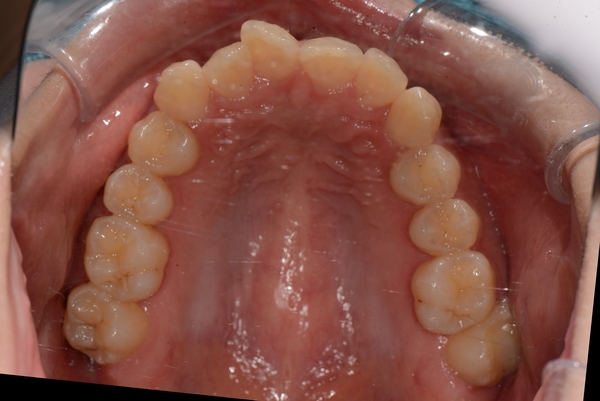

ガタガタとした歯並びや八重歯(叢生)CASE63